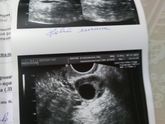

Кто разбирается в фотках, это что то серьезное или норм? узистка сказала что яичник увеличен, а почему не смогла ответить?в прошлом цикле было жт 17,4, потом пришли монстры, Узи я сделала на 5 дц вчера